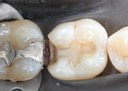

Matt Dodson #30 pre-op